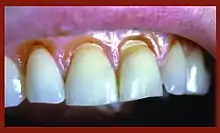

Clinical presentation of abfraction non-carious tooth tissue lesions on the cervical margins of upper left canine and premolar

When looking at abfraction lesions there are generally three shapes in which they appear, appearing as either wedge, saucer or mixed patterns.[6] Wedge and saucer shaped lesions are the most common, whereas mixed lesions are less frequently identified in the oral cavity.[6] In reference to figure 1, wedge shaped lesions have the sharpest internal line angles and saucer/mixed shaped lesions are either smooth internally, or a variety.